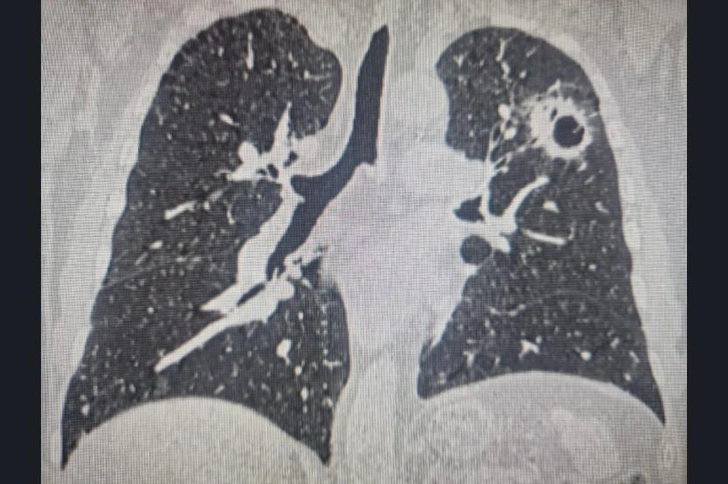

В первый раз сибиряку потребовалась помощь онкологов три года назад, тогда специалисты Новосибирского онкологического диспансера диагностировали у него центральный рак правого легкого. Обычно в таких случаях проводят пульмонэктомию, то есть удаляют легкое полностью.

Но в онкодиспансере решили сделать органосохраняющую операцию: удалили часть легкого с резекцией бронхов и сосудов, а после здоровые части органа сшили между между собой.

Первая операция позволила сохранить две трети легкого. Казалось бы, самое сложное позади. Врачи год пристально наблюдали за пациентом, что помогло вовремя выявить второй случай рака.

«Опухоль у мужчины развилась и в левом легком. Это были не метастазы после первого случая. Благодаря исследованиям вторую локализацию рака выявили на очень ранней стадии. В первый раз мы сохранили пациенту правое легкое, поэтому у бригады была возможность оперировать на левом», — говорит Вадим Козлов.

Выполнить операцию, когда у человека только одно легкое, невозможно, ведь во время процесса орган «отключат», пациенту станет нечем дышать. Однако правое легкое у мужчины функционировало, поэтому онкологи смогли провести вмешательство на левом.

Первая операция проводилась традиционным способом, обеспечивающим открытый доступ. Удаление сегмента второго легкого делали эндоскопически.